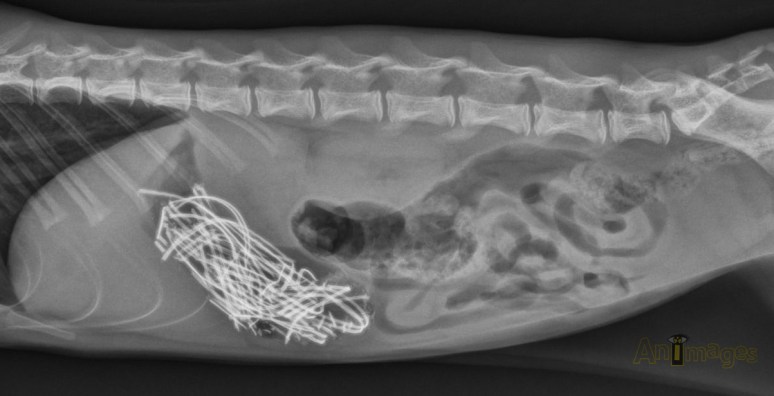

Ces radiographies d’un chat anorexique de 10 ans avec vomissements nous ont été soumises pour interprétation par la Dre Nathalie Therrien de l’Hôpital Vétérinaire du Coeur de Sherbrooke, qui a gracieusement accepté de partager ces images avec vous 🙂. Une exploration chirurgicale de l’abdomen a ensuite été réalisée.

Ce chien vomît depuis près d’une semaine. Quel est votre diagnostic ??